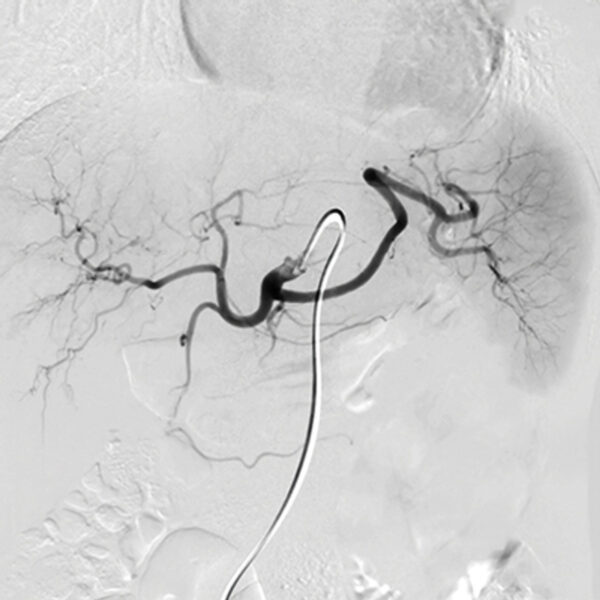

- Genicular Artery Embolization – Bedros Taslakian, MD